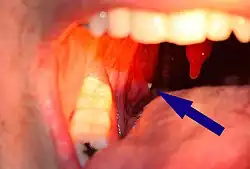

Tonsillensteine (auch Mandelsteine oder Tonsillolithe) sind wenige Millimeter große Gebilde aus dem Rachenraum von weiß-gelblicher Farbe und von weicher bis fester Konsistenz, die einen unangenehmen Geruch aufweisen. Sie können in den Krypten der Gaumenmandeln (Tonsilla palatina) – oder seltener in der Zungenmandel (Tonsilla lingualis)[1] – entstehen und bestehen aus Speiseresten und abgestoßenen Zellen der Schleimhaut. Tonsillensteine verursachen in der Regel keine Symptome und sind nicht behandlungsbedürftig.[2] Größere Tonsillensteine können Halsschmerzen oder Schluckbeschwerden verursachen[2], wobei sich kleinere Tonsillensteine meist spontan lösen. Weiterhin können Tonsillensteine eine Ursache für Mundgeruch sein.[3]

An den Kryptenöffnungen sichtbare Tonsillensteine können fälschlicherweise mit Fibrinbelägen einer Mandelentzündung (Stippchen) verwechselt werden. Beim ausschließlichen Vorhandensein von Tonsillensteinen fehlt es jedoch an Entzündungszeichen wie Rötung, Schwellung oder Halsschmerzen.